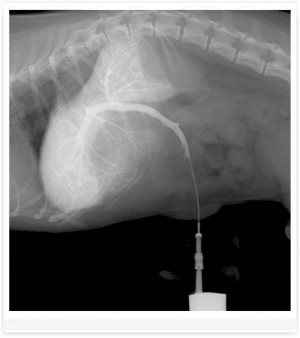

Foto 3. shunts portocaval - venei porte drenaj în vena cava caudală

Foto 4. shunts portocaval - venei porte drenaj în vena cava caudală

Foto 8. umplerea parțială a vaselor hepatice. Câine rasa Yorkshire Terrier.

Diagnosticul EXEMPLU și tratamentul shunt. Câine rasa Yorkshire Terrier